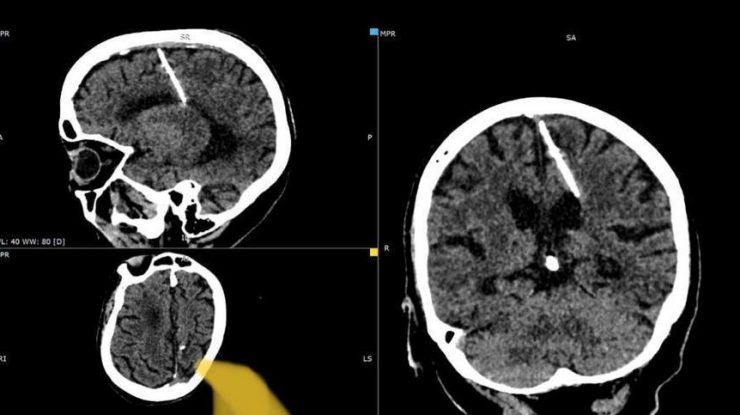

O femeie în vârstă din Rusia a trăit toată viața cu un ac de 3 cm lungime în creier. Medicii au făcut descoperirea neașteptată în timpul unei scanări CT, informează The Guardian.

Medicii cred că femeia, în vârstă de 80 de ani, a fost victima unei pruncucideri eșuate, comisă de părinții ei. Într-o declarație de miercuri, departamentul local de sănătate din îndepărtata regiune rusă Sahalin a spus: „Astfel de cazuri în timpul anilor de foamete nu erau neobișnuite.”

Părinții ei probabil au decis să-și omoare copilul în timpul celui de-al doilea război mondial așa cum fusese ea, trăind cu acul de 3 cm lungime „de la naștere”. Această metodă a fost adesea folosită pentru a ascunde dovezile crimei, se spune.

Penuria de alimente a fost răspândită în Uniunea Sovietică în timpul războiului și mulți oameni trăiau în sărăcie. „Acul i-a pătruns în lobul parietal stâng, dar nu a avut efectul scontat – fata a supraviețuit”, departamentul local de sănătate, adăugând că pacienta nu s-a plâns niciodată de dureri de cap din cauza rănii și nu a fost în niciun pericol. „Starea ei este monitorizată de medicul curant”, au spus medicii.